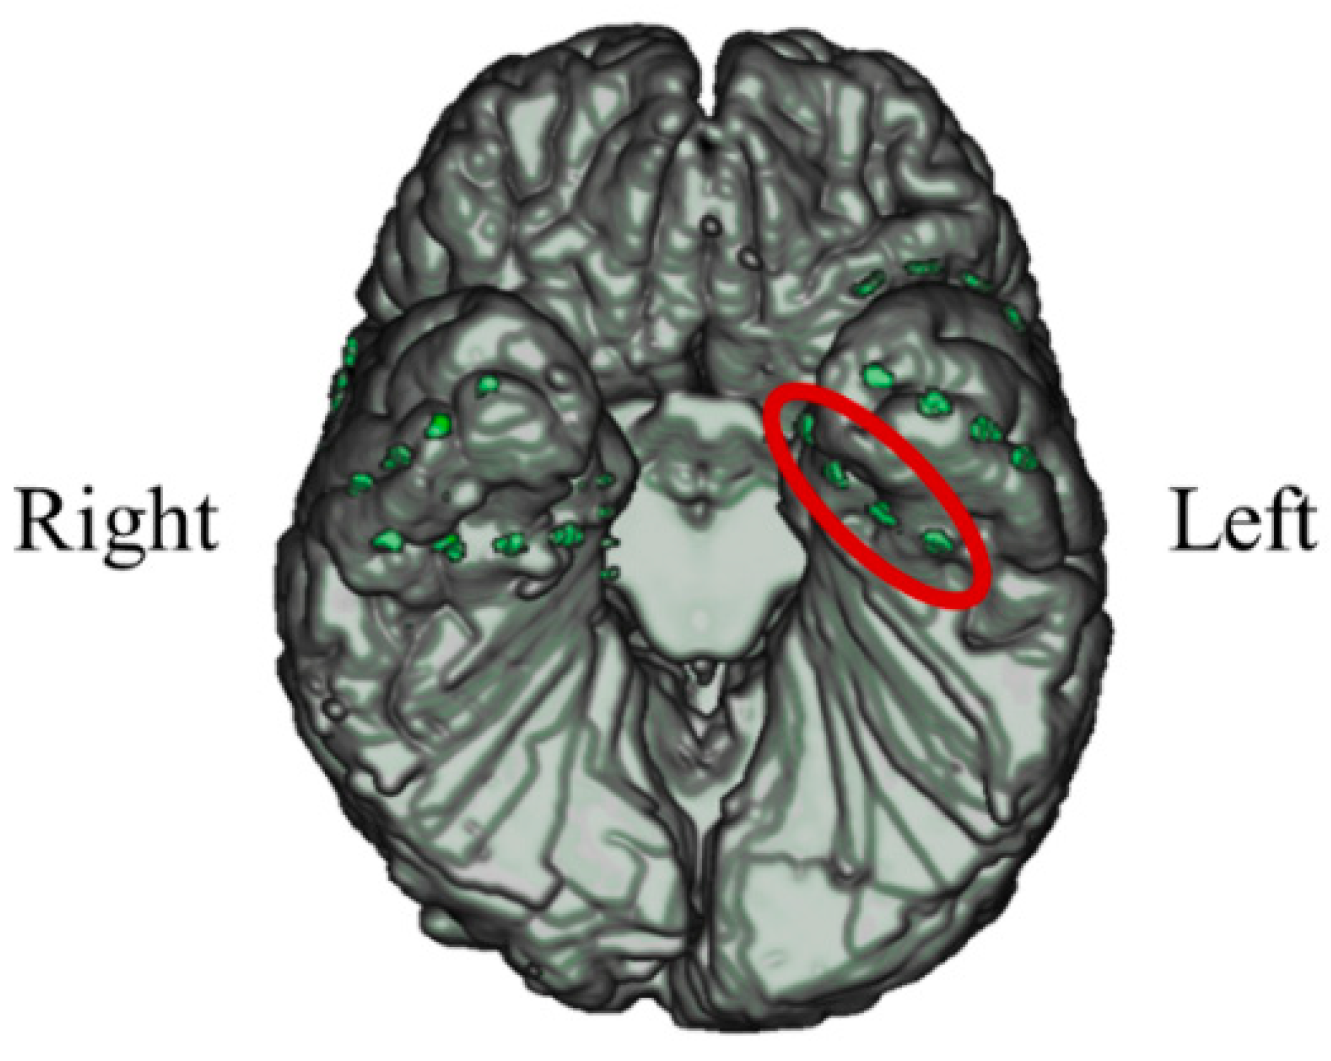

In P01, deep electrodes (Unique Medical, Tokyo, Japan) were implanted in the right MTL. The iEEG data were measured from four platinum electrodes (1 mm in length), positioned at 5 mm intervals (centre to centre) from the tip located in the right hippocampus, and used for NF (Figure 4). A reference electrode was placed subcutaneously on the right side for P01.